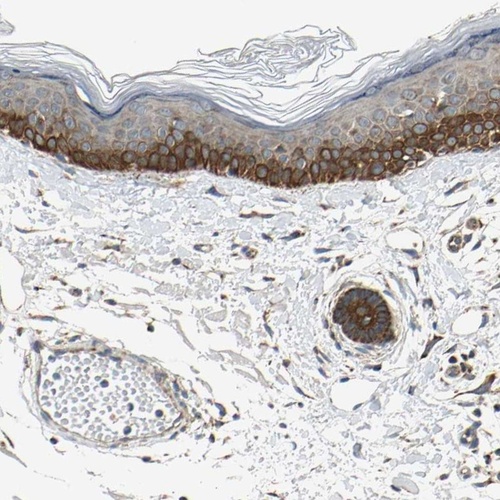

Immunohistochemical staining of human skin shows distinct cytoplasmic positivity in keratinocytes.